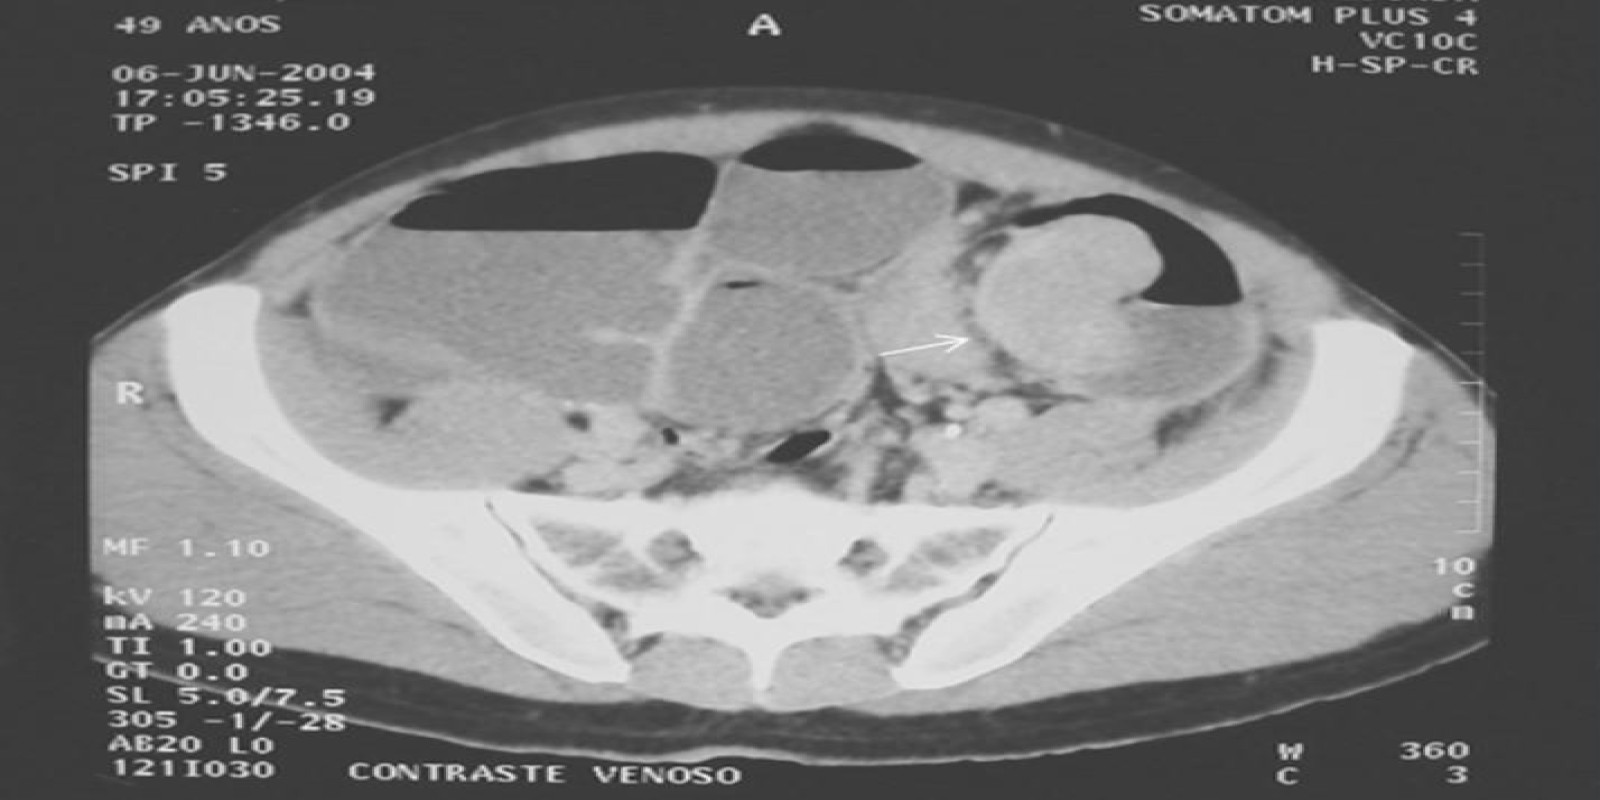

Caso Código 277A de Obstrução Intestinal do Cólon

Cod.: 277A